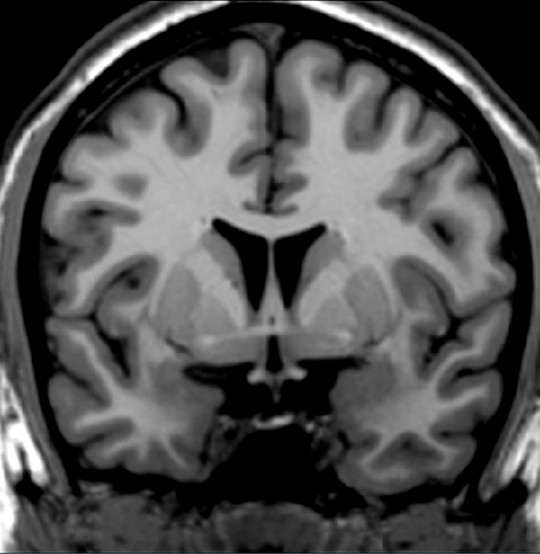

Identify one of the two regions that receive projections from the substantia nigra (pars compacta).